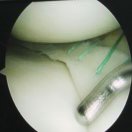

8:40—15:00  4例ACL全内重建、2例肩关节不稳手术演示

10:40—11:10    前交叉韧带的I.D.E.A.L重建    张磊教授